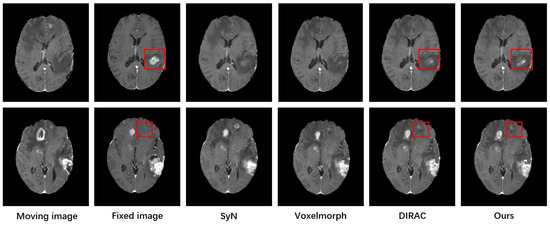

3.4. Comparative Experiment

3.4.1. Experiment Design

3.4.2. Results and Analysis